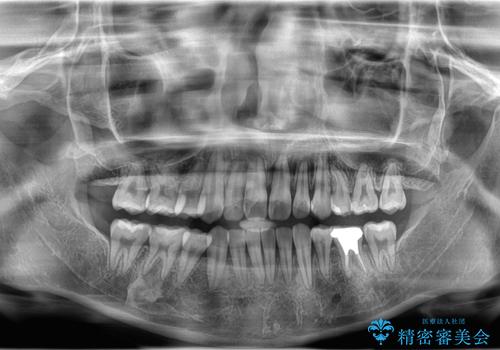

- 「歯のデコボコ、八重歯、口ボコが気になる」を主訴に来院された患者様です。

上下左右4番(4本)の歯を抜歯しワイヤー矯正で治療を行いました。

計4本の抜歯を行い、歯のデコボコと口元がすっきりし、大変ご満足していただけました。